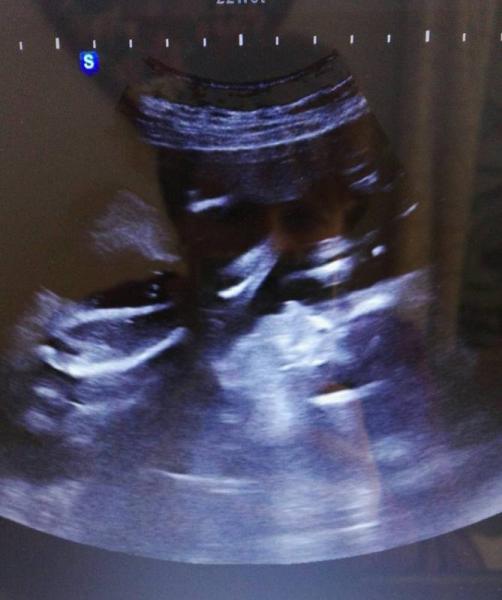

Alles super mit dem Zwerg! Er ist größer als sein Bruder (hoffe, dass er gerade einen Schub hatte und nicht sooo viel größer und schwerer ist als sein Bruder) Aber leider weiß ich heute weder Gewicht noch Größe. Aktuell liegt er in BEL und die Füße hat er am Kopf, also wie ein Klappmesser .

Danke ihr Lieben! Und ja, tatsächlich wie ein Klappmesser, seht selbst... von links unten nach rechts oben das Bein und rechts unten, das unscharfe, ist der Kopf, das Näschen sieht man ja